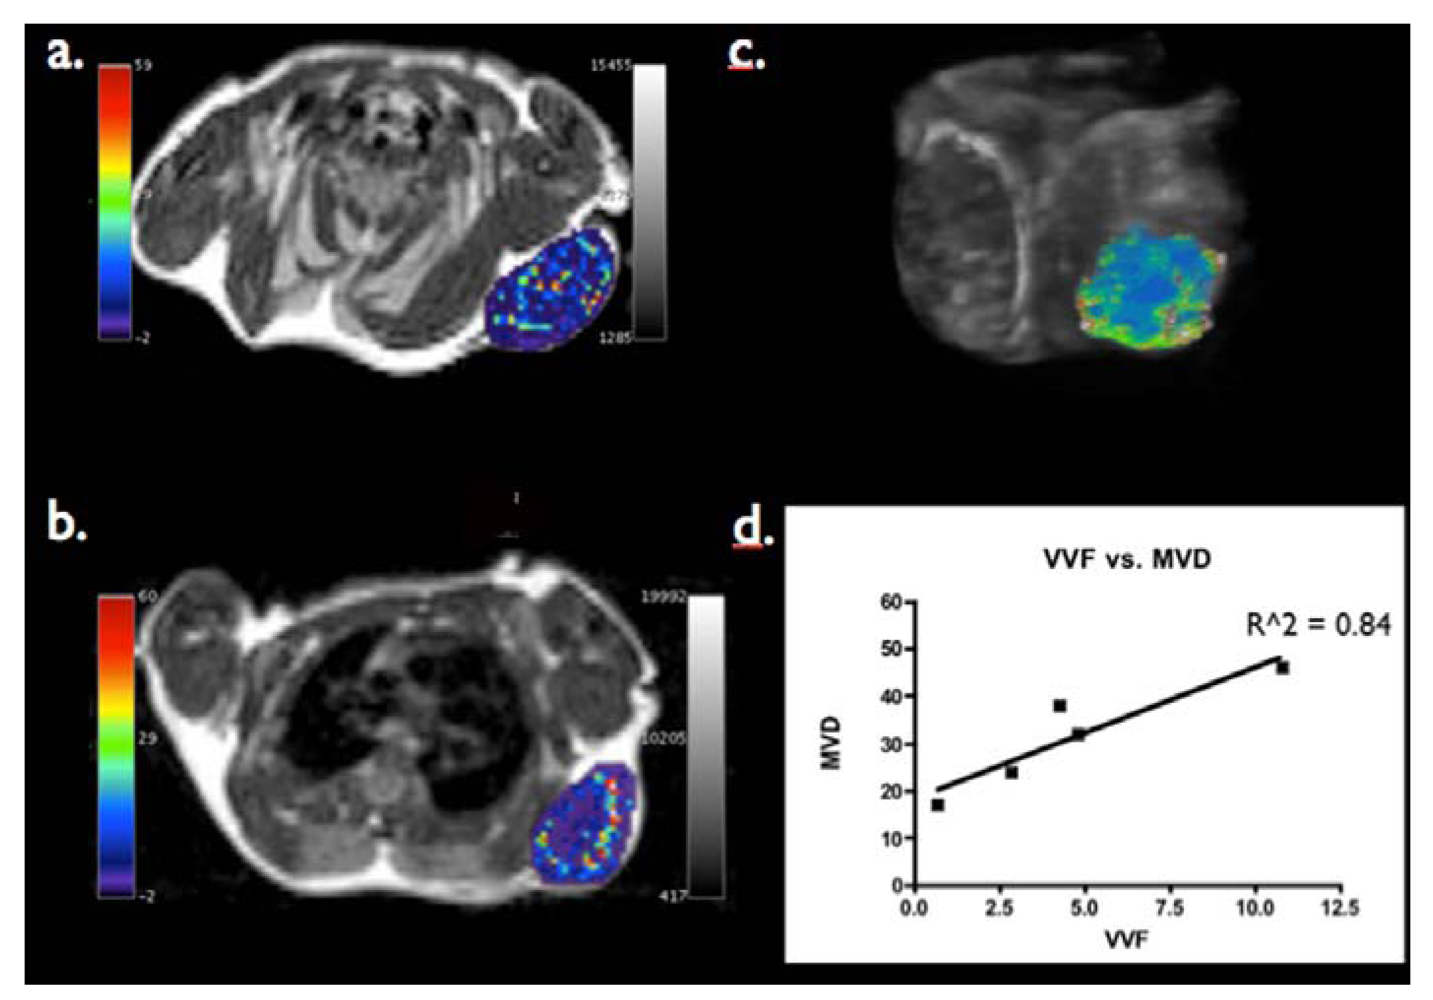

3.2. Can Steady State MRI Characterize Tumor Microvasculature?

- Bremer, C.; Mustafa, M.; Bogdanov, A., Jr.; Ntziachristos, V.; Petrovsky, A.; Weissleder, R. Steady-state blood volume measurements in experimental tumors with different angiogenic burdens a study in mice. Radiology 2003, 226, 214–220. [Google Scholar] [CrossRef]

- Hyodo, F.; Chandramouli, G.V.; Matsumoto, S.; Matsumoto, K.; Mitchell, J.B.; Krishna, M.C.; Munasinghe, J.P. Estimation of tumor microvessel density by MRI using a blood pool contrast agent. Int. J. Oncol. 2009, 35, 797–804. [Google Scholar]

- Valable, S.; Lemasson, B.; Farion, R.; Beaumont, M.; Segebarth, C.; Remy, C.; Barbier, E.L. Assessment of blood volume, vessel size, and the expression of angiogenic factors in two rat glioma models: A longitudinal in vivo and ex vivo study. NMR Biomed. 2008, 21, 1043–1056. [Google Scholar] [CrossRef]

- Beaumont, M.; Lemasson, B.; Farion, R.; Segebarth, C.; Remy, C.; Barbier, E.L. Characterization of tumor angiogenesis in rat brain using iron-based vessel size index MRI in combination with gadolinium-based dynamic contrast-enhanced MRI. J. Cereb. Blood Flow Metab. 2009, 29, 1714–1726. [Google Scholar]